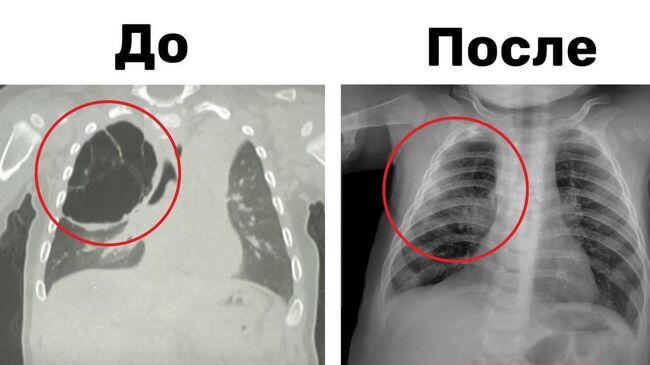

Леонид Рошаль основал научную школу в детской хирургии по разработке консервативных методов лечения у детей хирургических заболеваний, требующих раннего оперативного вмешательства. Им разработаны консервативные методы лечения острых хирургических заболеваний грудной и брюшной полости.